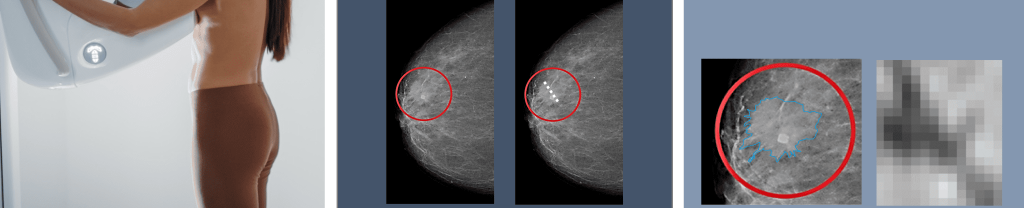

Ramona Woitek hat sich auf onkologische Bildgebung spezialisiert – entscheidend war für sie dabei, dass Brustkrebs häufig ist (eine von acht Frauen erkrankt) und Eierstockkrebs meist spät erkannt wird und daher eine schlechte Prognose hat. Am MIAAI testet sie verschiedene KI-Modelle, um automatisiert Tumore zu erkennen, sie zu klassifizieren, Tumorgröße und -volumen zu bestimmen, Charakteristika aufzuspüren, die mit dem menschlichen Auge nicht erkennbar sind und Vorhersagen zur Therapieansprache bzw. -abfolge zu machen. Denn wenn es in der Vielfalt von Krebserkrankungen einen Grundsatz gibt, so lautet er: Die bestmögliche Tumorbestimmung entscheidet über die bestmögliche individuelle Therapie.

Für Brust- und Prostata-Screening gibt es gute KI-Produkte, die von der reinen Bildinterpretation bis zur Biopsievorbereitung reichen, also gleich die ideale Stelle für eine Gewebeprobe identifizieren. Über die Krebs-Behandlung entscheiden in der Klinik interdisziplinäre Tumorboards im Team: Sie werten verschiedene Datenquellen (von Blutbefund bis Bilder) der Patient*innen aus und leiten daraus Therapie-Entscheidungen ab. So eine differenzierte, multimodale Entscheidungsvorbereitung klingt nach dem idealen Job für aufgabenorientierte, autonome „agentische KI“, die gerade in aller Munde ist: „Daran arbeiten viele Gruppen, weil es das tägliche Brot in der Krebsbehandlung ist. Das steckt aber noch in den Kinderschuhen. Es ist im Vergleich viel einfacher, hochspezialisierte Modelle zu trainieren.“ Das Training mit homogenen Datensätzen bringt keine KI-Modelle hervor, die auf die unordentliche, vielfältige und komplexe Realität gut vorbereitet sind. „Es würde mich also sehr überraschen, wenn in fünf Jahren ein KI-Agent bereits solche klinischen Entscheidungen unterstützt“, so Woitek.